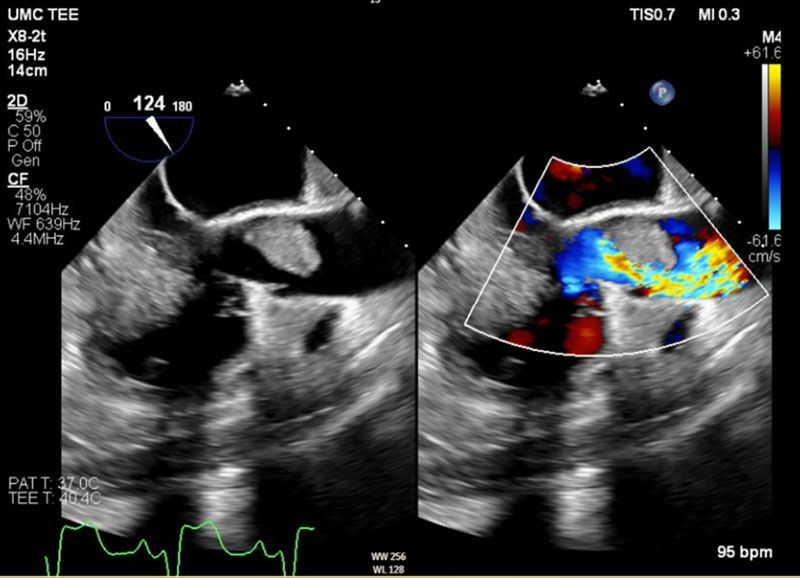

A 54-year-old male with a history of systemic lupus erythematous (SLE) and antiphospholipid syndrome (APS) on apixaban presented to the ED with symptoms and preliminary workup consistent with an ongoing non-ST-elevation myocardial infarction (NSTEMI). Prior to planned left heart catheterization (LHC), transthoracic echocardiogram identified a large thrombus/vegetation on his aortic valve. In light of this finding, the LHC was aborted to prevent catheter embolization of the lesion (engagement of the coronary arteries requires close catheter articulation with the aortic valve leaflets), and transesophageal echocardiogram (TEE) was subsequently performed to better visualize/characterize the mass. By TEE imaging, it measured up to 2.7 cm, nearly the diameter of the left ventricular outflow tract (LVOT) itself (Figure 1). The turbulent forward flow caused by functional LVOT stenosis (due to partial obstruction resulting from the large size of the mass relative to the outflow tract) was also appreciated (Figure 2), with mild to moderate aortic regurgitation also seen. After negative blood cultures suggested sterility of the lesion, this patient underwent surgical resection of the mass and replacement of his aortic valve with a tissue valve. Lack of growth on bacterial and fungal tissue culture from samples of the valvular vegetation obtained during surgery, in addition to his clinical history, provided support for the diagnosis of Libman-Sacks endocarditis. He had an uneventful postoperative inpatient recovery course before eventual discharge to home on warfarin.

Figure 1

Figure 1 TEE of the massive (2.7-cm) Libman-Sacks AV vegetation, with its relation to the size of the LVOT appreciated in cross-sectional short-axis view of the outflow tract just below the level of the AV.

TEE, transesophageal echocardiogram. AV, aortic valve. LVOT, left ventricular outflow tract.